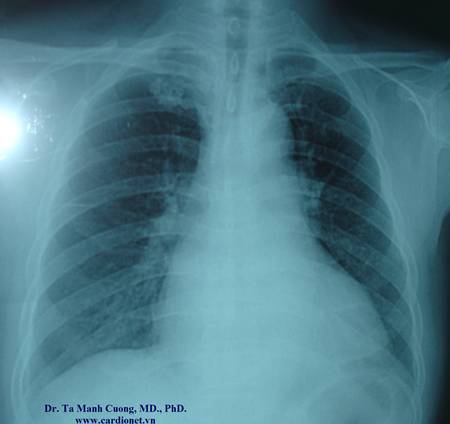

Hình ảnh đám mờ phổi phải khu trú, thành nhẵn ở một bệnh nhân suy tim độ 4. Bên cạnh đó có hình ảnh viêm rãnh liên thùy

Hình ảnh mờ này sau đó được nghĩ đến là tràn dịch màng phổi khu trú trên phim CT ngực. Sau 3 ngày điều trị bằng thuốc trợ tim, lợi tiểu và ức chế men chuyển, chụp lại Xquang tim phổi thẳng thì không còn hình mờ ở phổi phải nữa. Chẩn đoán: tràn dịch màng phổi rãnh liên thùy.